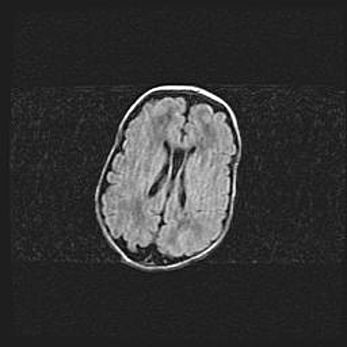

Наружная гидроцефалия с возможной атрофией височных областей.

Возраст: 28 дней

Вес: 3670 г

Пол: мужской

Окружность головы: 38 см

Срок гестации: 40 недель

Гидроцефалия головного мозга у новорожденных – это заболевание, которое характеризуется скоплением избыточного количества спинномозговой жидкости в желудочковой системе головного мозга в результате затруднения её перемещения от места выработки к месту поглощения в кровеносную систему или вследствие нарушения абсорбции. При открытой наружной форме гидроцефалии у новорожденных расширяются и переполняются субарахноидные пространства.

При нормотензивных  формах,  которые,  как  правило,  являются  следствием  перенесенных ишемических  повреждений  паренхимы  мозга,  возможно  сочетание микроцефалии  с нормотензивной гидроцефалией. В основе данных изменений лежит атрофия больших полушарий с преимущественной  локализацией  в  лобно-височных  областях.